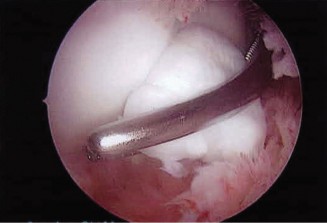

You send the patient for an MRI, which is shown in Figure 2–66.

Figure 2–66

Based on the clinical examination and imaging, what is the most likely etiology of the patient’s symptoms?

- Suprascapular nerve entrapment at the spinoglenoid notch by a paralabral cyst

The correct answer is (C). The patient’s clinical examination findings of isolated

weakness in external rotation and atrophy of the infraspinatus muscle point to suprascapular nerve entrapment at a location past the exit point for the branch to the supraspinatus muscle. Also, MRI reveals a posterior labral tear with a paralabral cyst that is compressing the suprascapular nerve at the spinoglenoid notch. Choice A, while fitting with the patient’s clinical examination, does not fit with the MRI showing paralabral cyst. Choices B and D are incorrect because entrapment of the suprascapular nerve at the suprascapular notch by scapular body fracture or by the transverse scapular ligament (more common) would lead to weakness/atrophy in both supraspinatus and infraspinatus muscles as the suprascapular notch is proximal to the nerve branch point to the supraspinatus muscle.